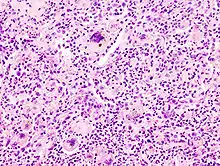

Langhans giant cells are named for the pathologist who discovered them, Theodor Langhans. Like many of the other kinds of giant cell formations, epithelioid macrophages fuse together and form a multinucleated giant cell. The nuclei form a circle or semicircle similar to the shape of a horseshoe away from the center of the cell. Langhans giant cell was typically associated with tuberculosis but has been found to occur in many types of granulomatous diseases.

Foreign-body giant cells form when a subject is exposed to a foreign substance. Exogenous substances can include talc or sutures. As with other types of giant cells, epithelioid macrophages fusing together causes these giant cells to form and grow.[13] In this form of giant cell, the nuclei are arranged in an overlapping manner. This giant cell is often found in tissue because of medical devices, prostheses, and biomaterials.